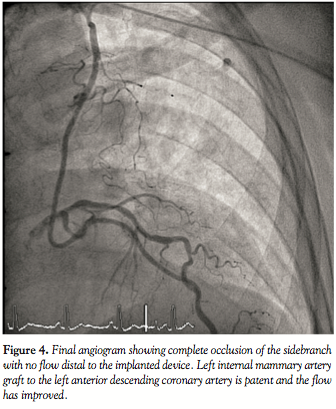

Through left radial arterial access, a 4 Fr diagnostic Judkins Right (JR) catheter

(Terumo Corporation Europe, Lueven, Belgium) was used to cannulate the LIMA. A 0.014˝ Balanced Heavy Weight (BHW) guidewire (Abbott Vascular, Santa Clara, California) was passed into the SB. The 4 Fr JR catheter was then advanced over the wire into the SB and the position was confirmed with contrast injection. The Amplatzer Vascular Plug 4 (AGA Medical, Golden Valley, Minnesota; Figure 5) was advanced into the SB using the delivery cable and the device was released by counter-clockwise rotation of the delivery cable.

Angiography confirmed excellent device position and complete occlusion of blood flow distal to the device with improvement of flow in the LIMA graft and LIMA-LAD flow (Figure 2). Following the procedure, the patient had complete resolution of his symptoms.